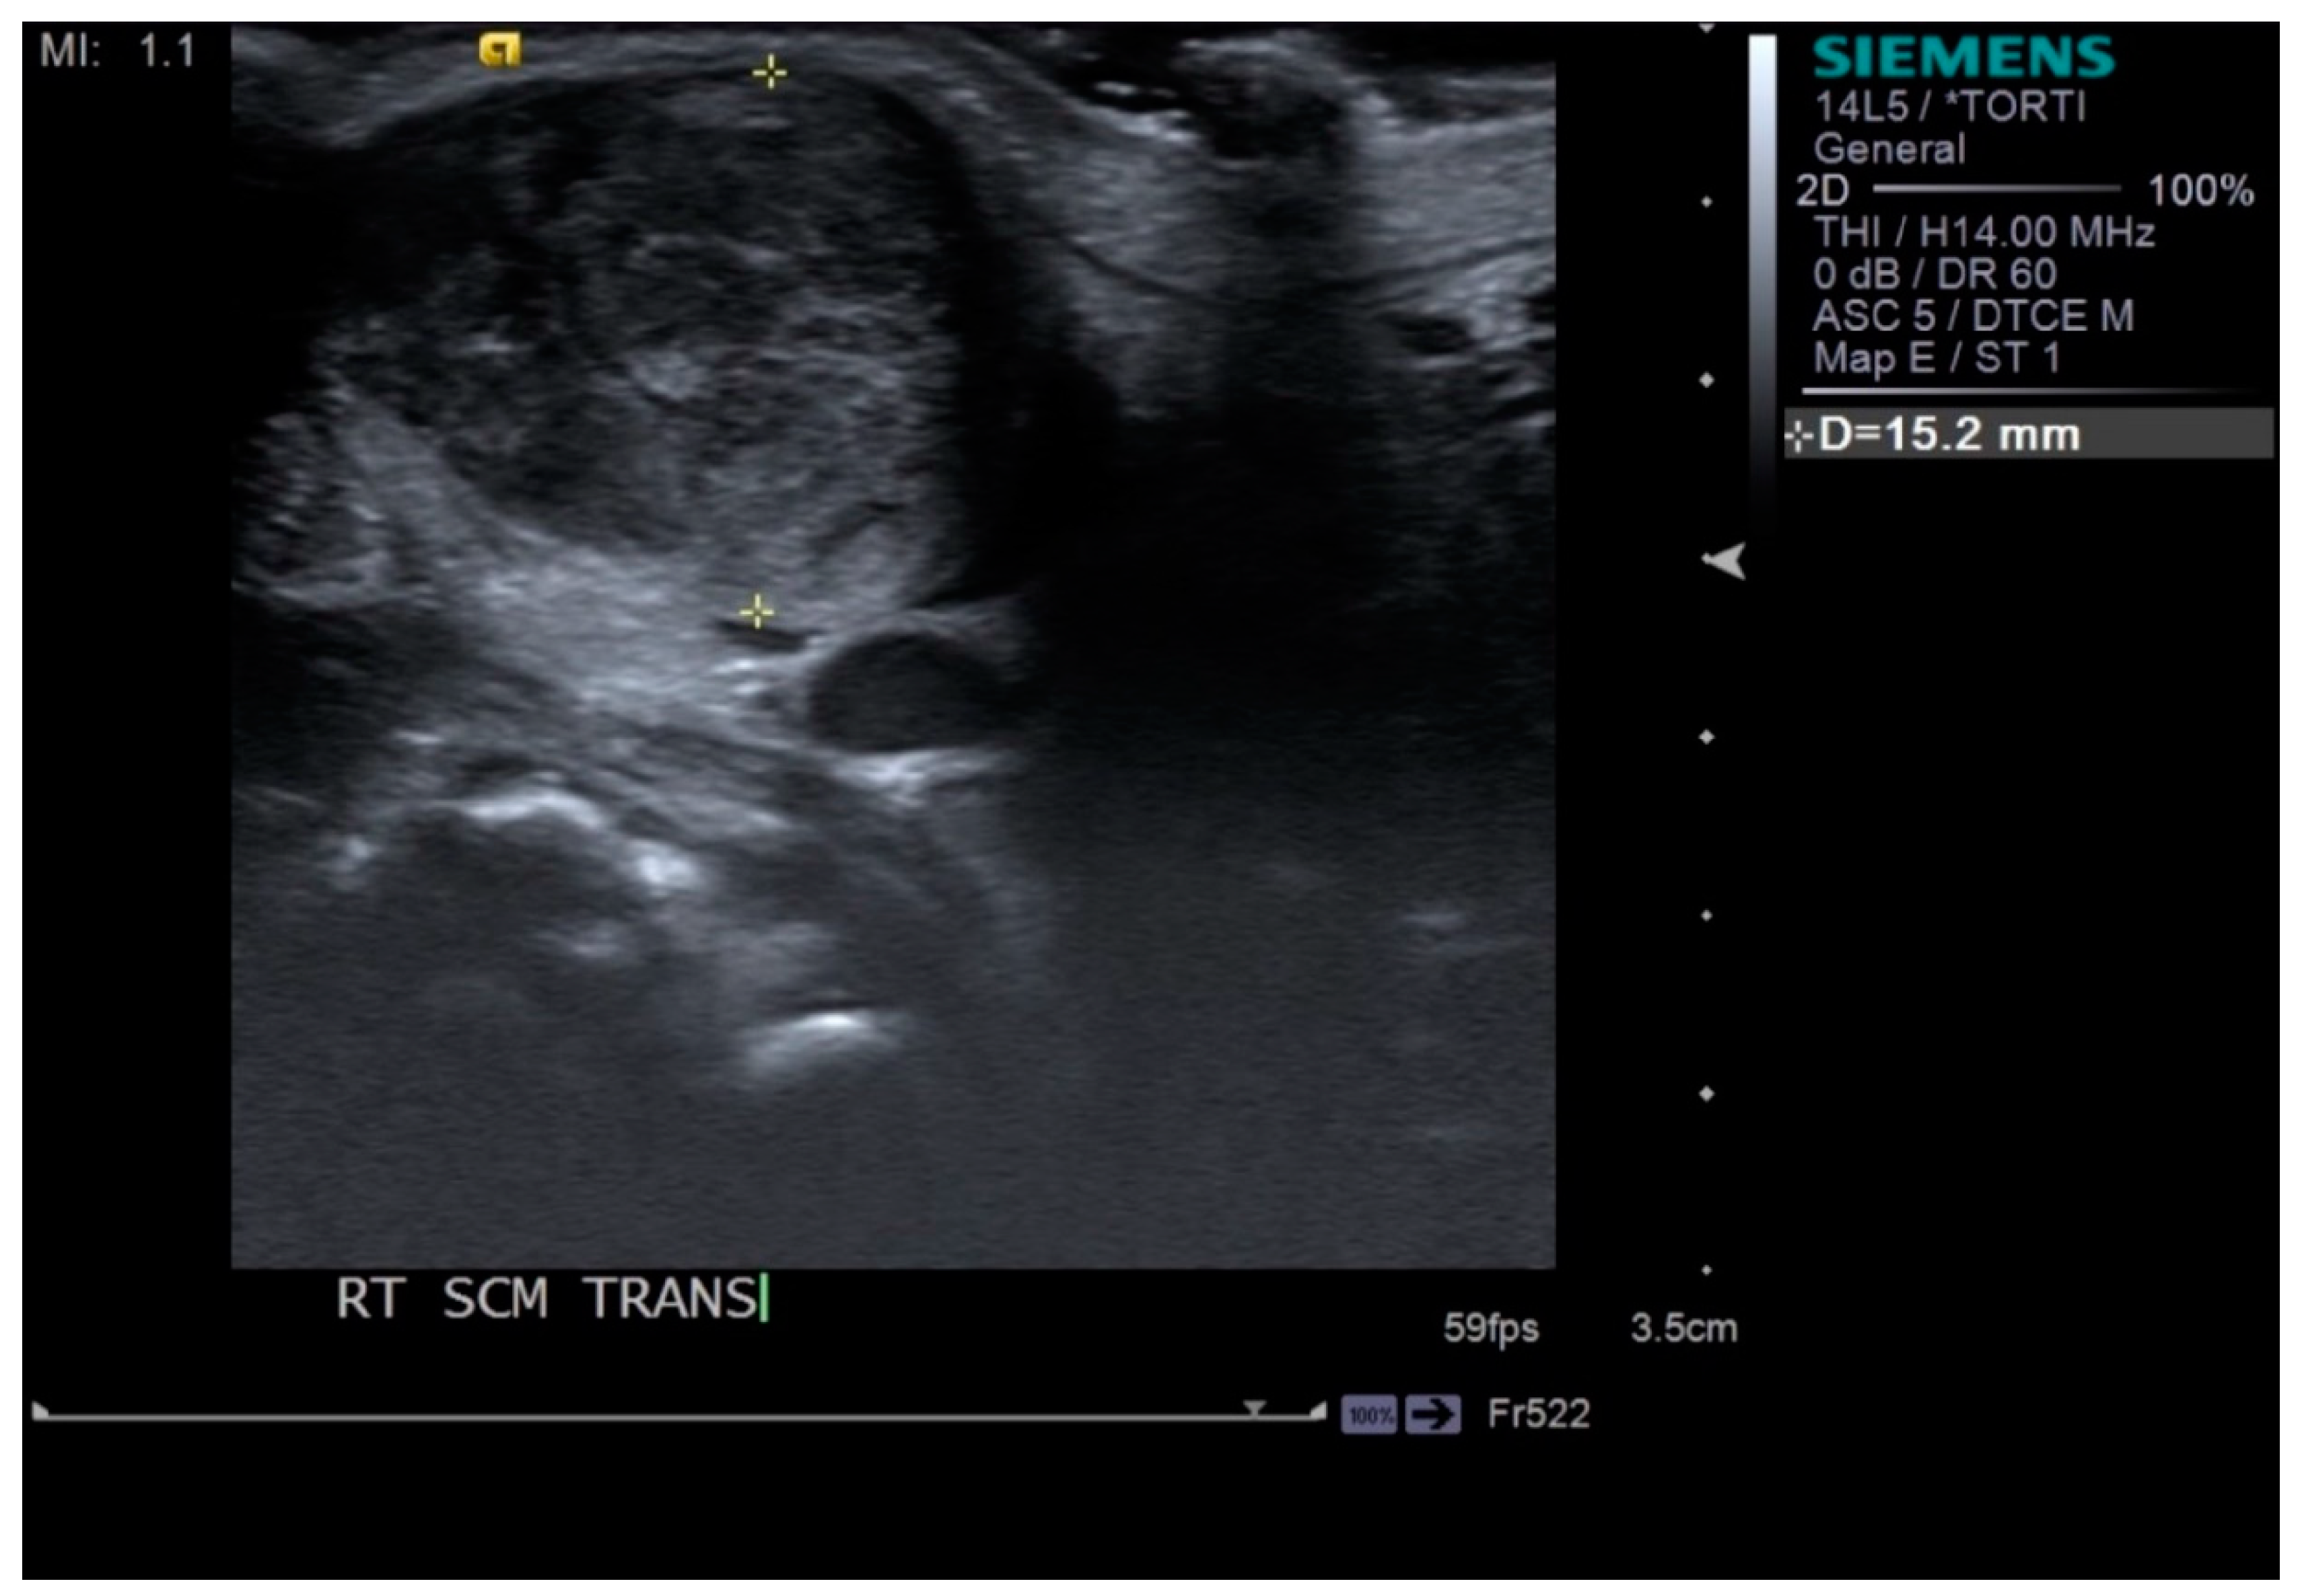

Neck ultrasonography was performed while the infants were asleep in a supine position, with slight rotation of the head to the opposite side. A small pillow was used to support the neck, and the infant’s position was also supported by the parents (Figure 1). Scanning was paused temporarily if the infant was uncooperative and cried. The ultrasound procedure was carried out by a skilled physiatrist with > 4 years of experience, using a Virtual Touch Imaging, ACUSON S2000 Ultrasound Unit (Siemens, Mountain View, CA, USA). The thickness of the affected SCM mass was measured in the longitudinal and transverse planes in ultrasound B mode with a linear probe of 5–14 MHz frequency bandwidth (Figure 2). The distance from the superficial to the deep fascia at the thickest portion of the SCM was measured using electronic calipers. The thickness of the unaffected SCM was also measured at the same level as the affected SCM. The SWV of the bilateral SCM was measured using ARFI in the transverse plane (Figure 3). The region of interest was selected to cover the entire SCM. Stronger manual compression increased the speed of shear-wave propagation, and the examiner therefore aimed to apply minimal compression during measurement of the SWV. SWV was measured three times at bilateral SCM muscles, and the median value was used for analysis. The ROM of neck rotation and lateral flexion were measured bilaterally using an arthrodial goniometer (Figure 4).

Figure 2.

Thickness of sternocleidomastoid (SCM) muscle measured by electronic calipers in the transverse plane.